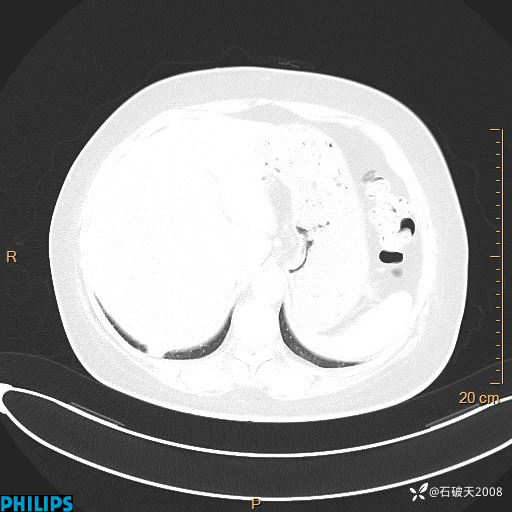

静脉期